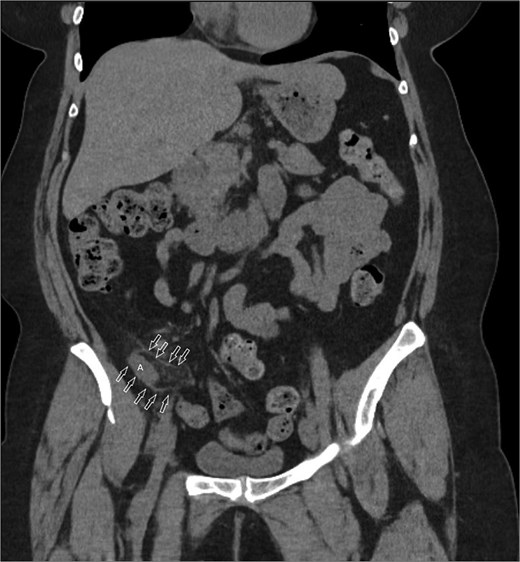

A 58-year-old female with a history of ovarian cancer, status post total abdominal hysterectomy, bilateral salpingo-oophorectomy, and omentectomy, presented with a 1-week history of right lower quadrant and right pelvic abdominal pain. Her labs were unremarkable. A CT scan of the abdomen and pelvis revealed a distended, fluid-filled appendix measuring 1.7 cm in diameter, with associated mesenteric infiltration and several small lymph nodes in the right lower quadrant, consistent with acute appendicitis (Fig. 1). The surgeon’s review of the scan was suspicious of retrocecal appendix (Fig. 2).

Coronal image CT scan with IV contrast with arrows denoting appendix in proximity to iliacus space. (A) Appendix.